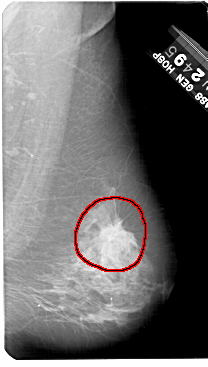

RIGHT_CC LINES 5461 PIXELS_PER_LINE 2821 BITS_PER_PIXEL 12 RESOLUTION 43.5 OVERLAY

RIGHT_MLO LINES 5491 PIXELS_PER_LINE 3106 BITS_PER_PIXEL 12 RESOLUTION 43.5 OVERLAY

FILE: A_1236_1.RIGHT_MLO.OVERLAY

TOTAL_ABNORMALITIES 1

ABNORMALITY 1

LESION_TYPE CALCIFICATION TYPE PLEOMORPHIC DISTRIBUTION CLUSTERED

LESION_TYPE MASS SHAPE IRREGULAR MARGINS SPICULATED

ASSESSMENT 5

SUBTLETY 5

PATHOLOGY MALIGNANT

TOTAL_OUTLINES 1

BOUNDARY